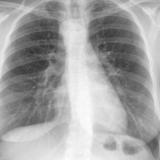

ASD 2 PA

Date: 03/17/2004

Views: 2413